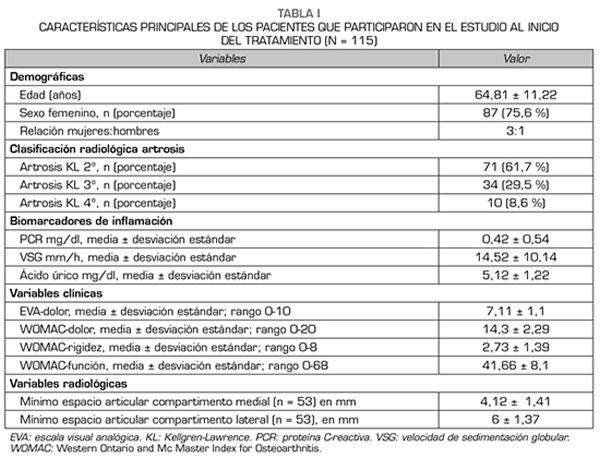

En este estudio se evaluaron 115 pacientes. La edad media de los pacientes fue de 64,81 ± 11,22 años. Los pacientes femeninos representaron el 75,6 % (n = 87), mientras que los pacientes masculinos correspondieron al 24,4 % (n = 28), con una proporción de mujeres: hombres de 3:1 (Tabla I).

El grado radiológico más frecuente fue KL 2º (n = 71; 61,7 %), seguido de KL 3º grado (n = 34; 29.5 %) y KL 4º grado (n = 10; 8,6 %) (Tabla I).